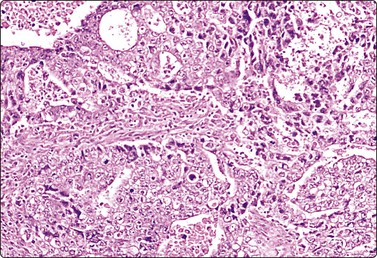

Tumors of more than one histologic type (mixed forms) (Figs 13.35 and 13.36)14,60,63,65

While the basic GCT types are infrequent in pure forms they are very frequent in mixed forms. Embryonal carcinoma and teratoma are each present in 47% of cases, and yolk sac tumors in 41%; 40% of TGCT contain varying numbers of syncytiotrophoblastic cells.12

image

Fig. 13.35 Tumor of more than one histological type (mixed form)

Large bisected tumor occupying most of the enlarged testicle in a male 19 years of age. Note hyalinized, degenerate and cystic areas.

image image

Fig. 13.36 Tumor of more than one histological type (mixed form)

(A) Well-differentiated glandular epithelium (right), large malignant cells similar to embryonal carcinoma (left) (MGG, HP); (B) Corresponding tissue section (A, H&E, IP; B, PAP, IP).

Criteria for diagnosis

Cellular aspirates; necrosis and hemorrhage frequent,

Three-dimensional clusters of epithelial malignant cells as described above

Coexisting teratomatous structures represented by mature or immature tissues originating from one or more blastodermal leaf: fusiform naked nuclei embedded in a myxoid background resembling embryonal mesenchyme; islets of cartilage; sheets of epithelial cells, which may be squamous, ciliated or intestinal (with goblet cells); bundles of fusiform cells with blunt ends reminiscent of leiomyoma; tight clusters of deeply stained bare nuclei may correspond to primitive neuroectodermal tissue.

The diagnosis of mixed forms is simple when malignant elements of an epithelial nature coexist with clear-cut teratomatous structures. Necrosis may obscure the neoplastic cells and the teratomatous component may be only minor or even absent. This can be explained by its greater cohesion causing under-representation in FNA samples. As a result, the differential diagnosis between mixed TGCT and embryonal carcinoma is sometimes difficult or impossible.14,59-61,65,66 The presence of multinucleated syncytial cells is not diagnostic of choriocarcinoma.